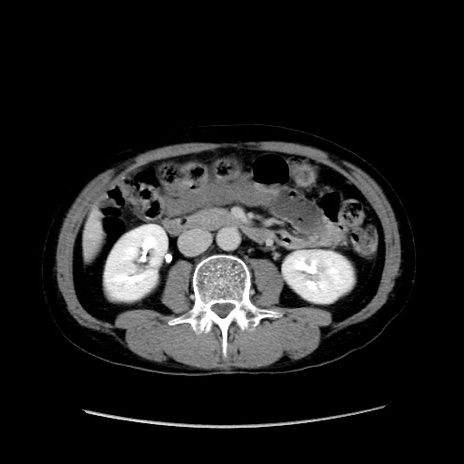

冠状断像

症例37(横断像)

【症例】40歳代 男性

【主訴】腹痛

【現病歴】4時間ほど前に電車に乗車中に臍部上より腹痛出現。徐々に増悪し起立困難となり、救急外来受診。生ものは数日食べていない。今朝お雑煮を食べた。

【身体所見】BT 36.8℃、BP 117/84mmHg、HR 91/min、SpO2 97%、苦悶様、腹部:臍上部広範囲圧痛あり、反跳痛±

【データ】WBC 8100、CRP 0.03